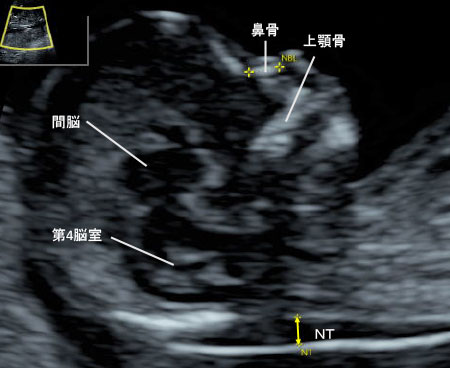

先天異常部より Nt Nuchal Translucency について 医療者向け 日本産婦人科医会

Nt Nuchal Translucency ある産婦人科医のひとりごと

14 初期の超音波マーカー検査 日本産婦人科医会

胎児エコーの最新動向 新 超音波診断 Vol 02 東芝メディカルシステムズ株式会社 Innavi Suite

先天異常部より Nt Nuchal Translucency について 医療者向け 日本産婦人科医会

胎児エコーの最新動向 新 超音波診断 Vol 02 東芝メディカルシステムズ株式会社 Innavi Suite

妊娠初期超音波の出生前診断における役割 Fetal Skeletal Dysplasia Forum

02 妊娠初期 胎児の頸部浮腫 Nt 妊娠11 13週でcheck 深谷産婦人科 医学情報

胎児超音波ーマーカー検査とは ヒロクリニック

妊娠初期超音波の出生前診断における役割 Fetal Skeletal Dysplasia Forum

胎児の首の後ろのむくみ 浮腫 Nt とは 妊娠初期 All About

Nt Nuchal Translucency について 出生前検査 Nipt 遺伝カウンセリング 妊婦健診 エコー検査 産科 婦人科 産婦人科

胎児の首の後ろのむくみ 浮腫 Nt とは 妊娠初期 All About